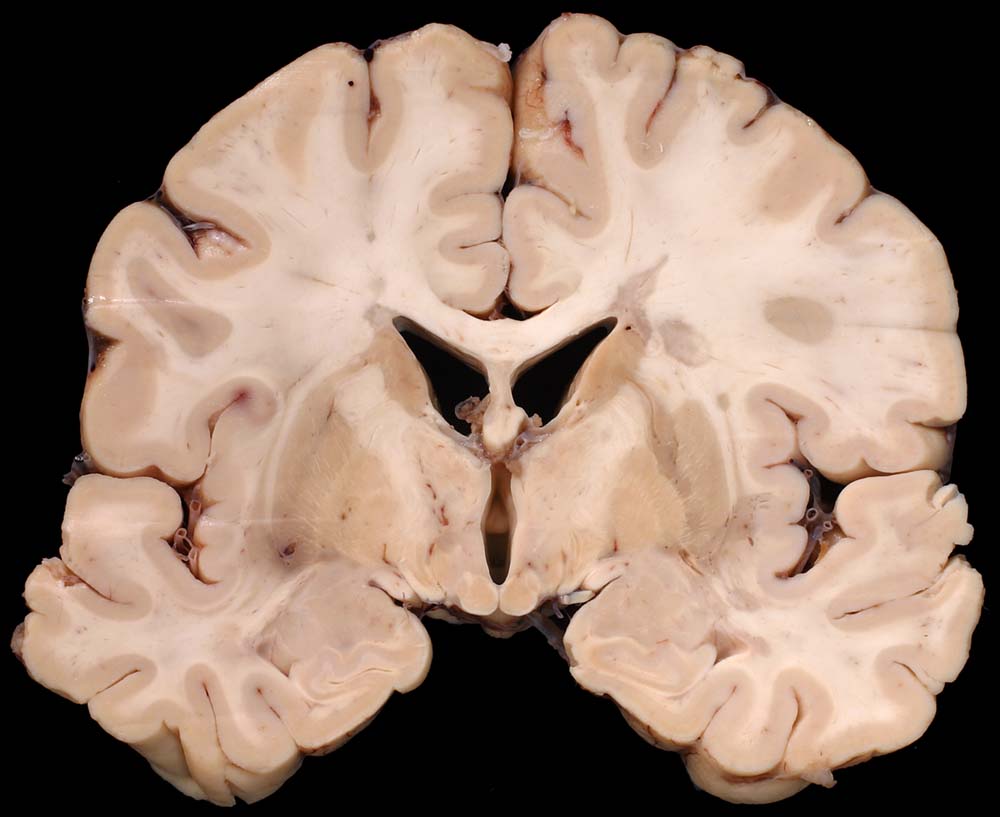

PathoPic ID 8793 - Periventrikulär betonte Entmarkungsherde bei multipler Sklerose

Periventrikulär betonte Entmarkungsherde bei multipler Sklerose

Periventrikulär betonte irregulär begrenzte

Grauverfärbung des Marklagers.

Multiple Sklerose (Erstdiagnose vor 30 Jahren) mit spastischer Paraparese und neurogener Blasenmotorikstörung.